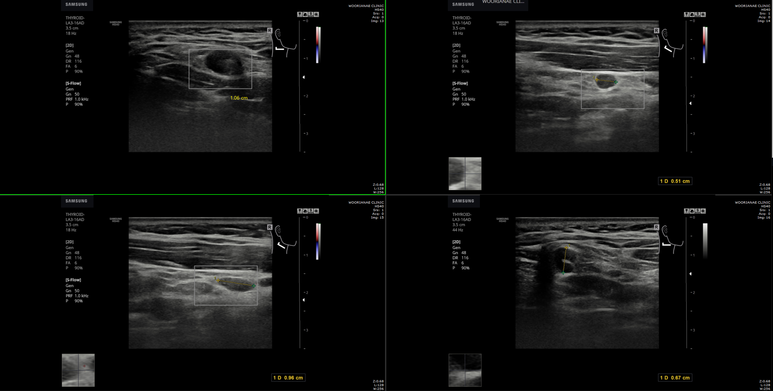

10 mm를 초과하는 림프절들이 area III~II, SCM 위쪽에 2개 관찰; hilum의 지방 구조가 관찰되나 둥그렇고 켜져있다.

경동맥, 경정맥 외측으로 작은 림프절이 다수; hilum의 지방 구조가 관찰되지 않는다.

갑상선에 저음영의 결절이 8 mm 크기, TIRAD 4A 정도의 undetermined 양상 (악성 확율 5~10%)